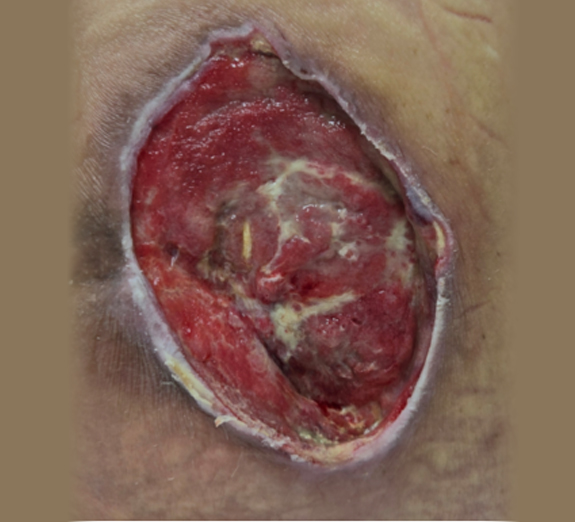

심부욕창 치료 사례

• 치료 전

• 치료 후